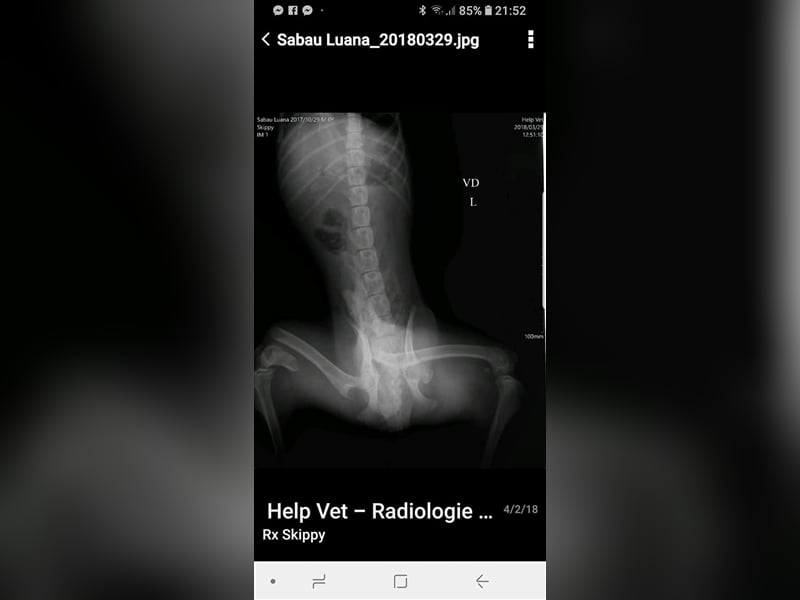

Skipper wurde im Oktober 2017 geboren, hat eine Schulterhöhe von knapp 50 cm und ist kastriert. Der Rüde wurde verletzt im Straßengraben gefunden, beide Hinterbeine waren gebrochen, doch er konnte erfolgreich operiert werden. Er ist inzwischen wieder flott auf seinen vier Beinen unterwegs, auch wenn sein Bewegungsablauf nicht ganz rund ist, so schränkt ihn seine minimale Behinderung nicht ein, fällt auch kaum auf und er ist auf seinen vier Beinen flott unterwegs. Der hübsche Rüde wird vielleicht nicht der ideale Begleiter für längere Joggingrunden oder Radtouren sein, aber nicht jeder Mensch ist ein Sportfreak und Skipper ist auf keinen Fall ein Couchpotato. Skipper lebt seit Juli bei einer Pflegefamilie in Dortmund zusammen mit anderen Hunden und kann dort gerne kennengelernt werden.